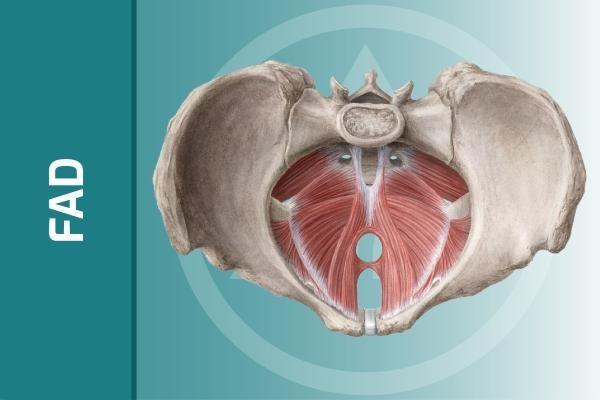

Il pavimento pelvico rappresenta la chiusura inferiore del bacino e corrisponde all'area genito-urinaria e anale. In tale zona, al di sotto di pelle e mucose, è presente tessuto muscolare così come in tutto il corpo umano. Il pavimento pelvico è costituito oltre che da muscoli, organizzati in tre diversi strati più o meno profondi nel bacino, anche da tessuto connettivo ovvero da legamenti e fasce.

I visceri pelvici come vescica e uretra, utero e canale vaginale nella donna, retto e canale anale sono poggiati sui muscoli e sul connettivo che compongono il pavimento pelvico, che può essere pertanto paragonato a un'amaca. Inoltre uretra e canale anale nella loro parte finale attraversano il pavimento pelvico il quale determina quindi intorno a essi fibre muscolari ad andamento circolare che sono gli sfinteri, rispettivamente uretrale e anale. Anche il canale vaginale nella sua parte finale è circondato ad anello dalle fibre del pavimento pelvico. Il pavimento pelvico si estende dal pube, in avanti, al coccige e al sacro all'indietro, mentre lateralmente si attacca in parte direttamente alle ossa del bacino, in parte si inserisce su altri muscoli o strutture connettivali. Da questi punti di origine, quasi tutte le fibre muscolari prendono contatto con una grossa formazione tendinea facilmente individuabile dall'esterno, situata tra l'ano e la vagina nella donna e tra l'ano e la base del pene nell'uomo, chiamata centro tendineo del perineo. Per indicare il pavimento pelvico vengono usati talvolta altri termini come perineo, diaframma pelvico, muscolatura sfinteriale o altri ancora. In realtà ognuno di questi termini rappresenta una porzione di tutta la zona.